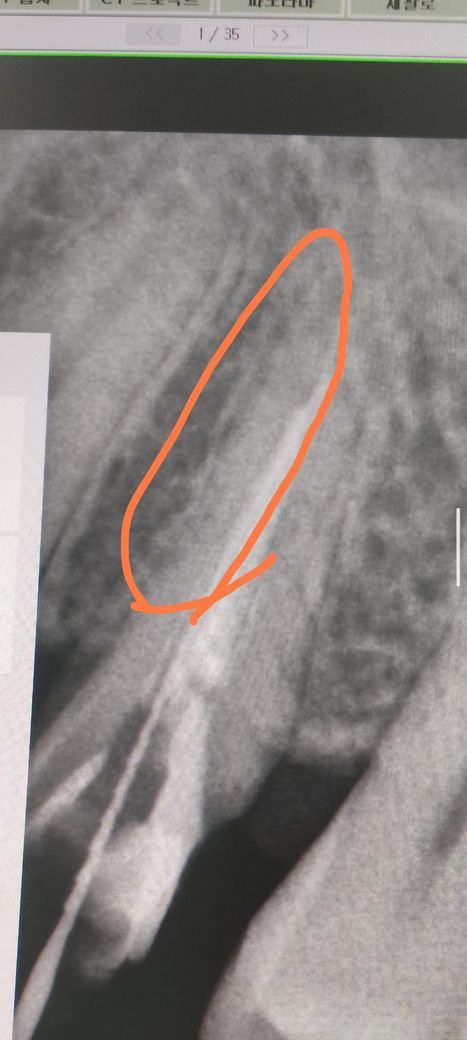

치아파절된거 같은데 발치해야되나요? 사진보시구 답변주심 감사합니다.

뽀족한것을 잇몸으로 동그라미친 부분에 넣어보니 쭉들어가더라구요 아무래도 치아가 사진속 동그라미친 부위모양으로 파절되서 그쪽으로 음식물이 들어가거나 씹을때 파절된

치아조각이 뿌리치조골쪽을 게속 찌르니까 신경과민 예민생겨서

사진속 동그라미친 부위 모양으로 파절된게 거의 확실한거같은데 한번 사진 봐주시면 감사합니다. 혹시 저모양으로 파절됬으면 파절조각만 제거해서 남은치아로

• 2번 째 사진

해당 치아 뿌리가 2개인 형태로 보입니다 maxillary second premolar 2 root 구글에 검색해서 엑스레이 사진이나 실제 사진 참고하시고요

그와는 별개로 신경치료나 재신경치료를 했는데도 증상이 지속되면 어딘가 뿌리쪽에 크랙이 있어서 그럴 수도 있습니다 엑스레이 상으론 명확히 보이진 않으나 증상이 그렇다면 맞을겁니다

빼는 방법밖에 없을 것 같네요

아쉽지만 뿌리쪽 파절편만 제거한다는 방식은 치과치료에 없습니다